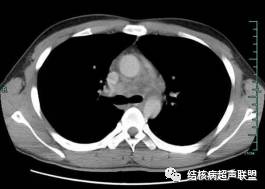

CT可见纵隔内多发肿大淋巴结